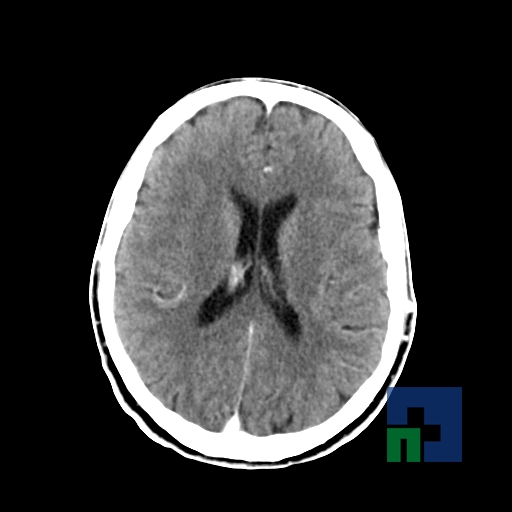

Examinare de rutină cerebrală, nativ și cu substanță de contrast (SDC) pentru diagnosticul:

- Accidentelor vasculare cerebrale ischemice sau hemoragice

În cazul traumatismelor cranio-cerebrale:

- Evaluarea deplasării liniei mediane

- Evaluarea cisternelor perimezencefalice

- Diagnosticul edemului cerebral, a contuziei cerebrale, a leziunilor axonale difuze edematoase/hemoragice, a dilacerării cerebrale, a hematomului intraparenchimatos posttraumatic, a hematoamelor subdurale/extradurale (acute, subacute, cronice), a hemoragiei intraventriculare, a hemoragiei subarahnoidiene

- Diagnosticul traumatismelor de bază de craniu

- Diagnosticul fistulei LCR

- Diagnosticul herniilor cerebrale

- Diagnosticul fracturilor:

- Tumorilor cerebrale:

- Empiemul subdural

- Abcesul cerebral

- Fistula carotido-cavernoasa

- Higroma

- Atrofia cerebrală regională